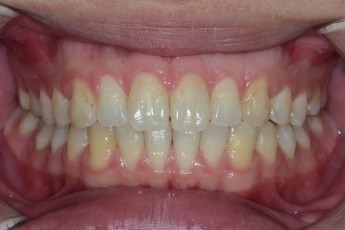

Before

After